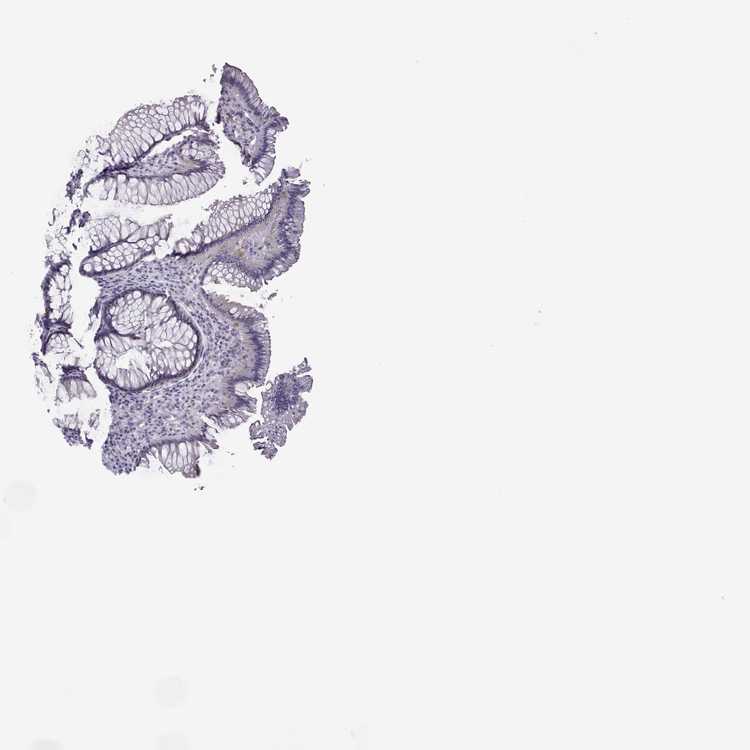

TISSUE PRIMARY DATA RECTUM Show tissue menu

RECTUM - Antibody stainingi

Antibody staining in the annotated cell types in the current human tissue is reported as not detected, low, medium, or high, based on conventional immunohistochemistry profiling in selected tissues. This score is based on the combination of the staining intensity and fraction of stained cells.

Each image is clickable and will lead to virtual microscopy that enables deeper exploration of all samples and also displays staining intensity scores, fraction scores and subcellular localization as well as patient and tissue information for each sample.

Antibody HPA073521

Glandular cells Low